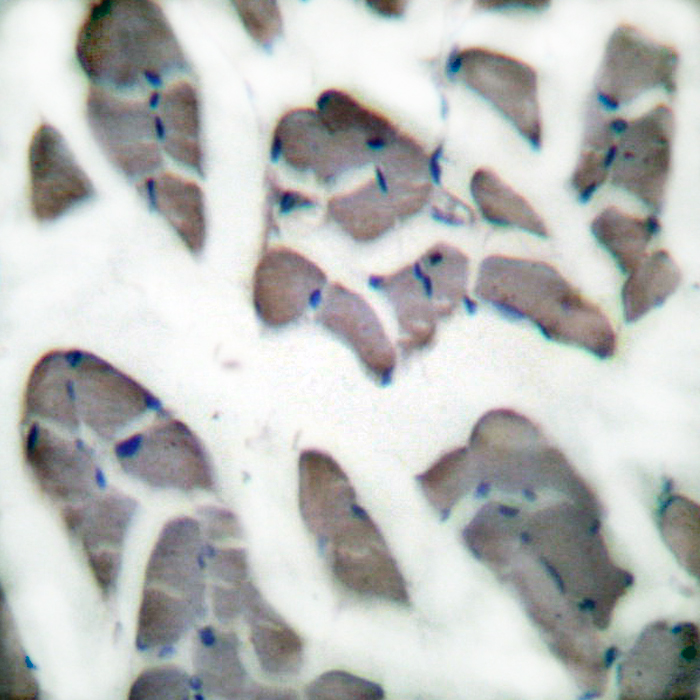

IHC 1/50-1/100 Human,Mouse,Rat

ICC 1/50-1/200 Human,Mouse,Rat

In research and diagnostics, desmin antibodies are widely employed to identify muscle-specific tissues and tumors through techniques like immunohistochemistry (IHC), immunofluorescence (IF), and Western blotting. Their specificity makes them valuable in distinguishing sarcomas (e.g., rhabdomyosarcoma, leiomyosarcoma) from non-muscular neoplasms. Additionally, desmin expression patterns aid in studying muscle regeneration, myopathies, and cardiomyopathies. Mutations in the desmin gene (*DES*) are linked to desmin-related myofibrillar myopathies, characterized by protein aggregation and muscle degeneration. Desmin antibodies also help assess pathological changes in cardiac diseases, such as ischemia or hypertrophy, where desmin reorganization or loss correlates with functional impairment. However, cross-reactivity with other intermediate filaments or degraded proteins requires careful validation. Overall, desmin antibodies remain essential in both basic muscle biology research and clinical pathology for understanding and diagnosing muscle-related disorders.